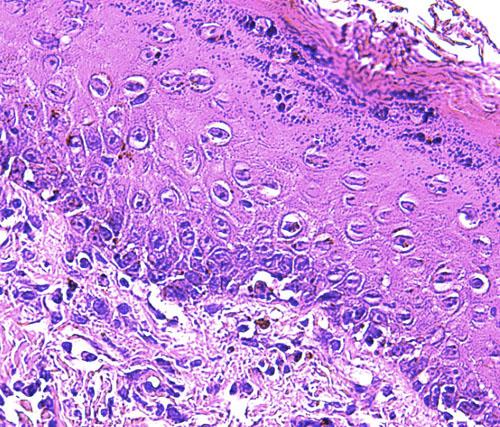

Photo 12 (Hémalun-Eosine X100): vue rapprochée d’une papille ostiale.

Elle est revêtue d’un chapeau parakératosique au sein duquel les kératinocytes sous-cornés sont vacuolisés.

Légendes de la Photo 12 :

- Flèche truquoie : sommet d’une projection papillaire de l’épiderme hyperplasique se formant à la marge d’un ostium folliculaire

- Double flèche orange pointillée : épiderme (portion non kératinisée)

- Double flèche verte : derme

- Rond marron : tige pilaire

- Ovales turquoises : infundibula folliculaires hyperkératosiques (orthokératose)

- Étoiles rouges : infiltrat inflammatoire dermique péri-vasculaire

- Flèche jaune : parakératose coiffant la papille épidermique

- Etroile rouge vide : le sommet de la paille épidermique montre une ballonisation des kératinocytes

Photo 13 (Hémalun-Eosine X200) : vue rapprochée d’une papille ostiale de la Photo 12.

Elle est revêtue d’un chapeau parakératosique au sein duquel

les kératinocytes sous-cornés sont vacuolisés (vacuole cytoplasmique).

Légendes de la Photo 13 :

- Rond marron et ovale turquoise : infundibulum folliculaire hyperkératosiques (orthokératose)

- Rond turquoise : zone granuleuse de la papille épidermique

- Flèche jaune : kératinocytes au cytoplasme vacuolisé

- Etroiles rouges : zone de parakératose, coiffe parakératosique de la papille épidermique